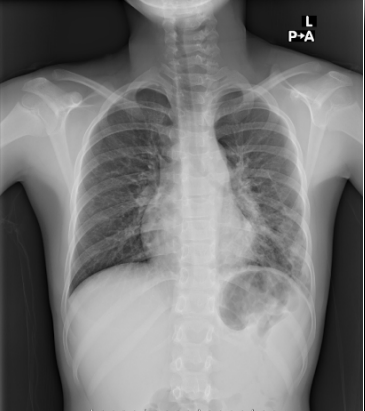

Pneumonia is one of the most common conditions encountered by primary care providers. Certain organisms cause pneumonia in particular age groups. For example, group B streptococci, Gram-negative bacilli Escherichia coli in particular) and, rarely, Listeria monocytogenes cause pneumonia in neonates. In infants younger than 3 months, group B streptococci and organisms encountered by older children occasionally cause pneumonia, as does Chlamydia trachomatis. Older infants and preschoolers are at risk for infection with Streptococcus pneumoniae and Haemophilus influenzae. In children older than 5 years, S pneumoniae and Mycoplasma pneumoniae are the key pathogens. Let the patient's age, history, clinical presentation, and radiographic findings guide your choice of therapy. Even though most patients with uncomplicated pneumonia can be treated as outpatients, close follow-up is important. Hospitalize patients younger than 6 months and those with complications.